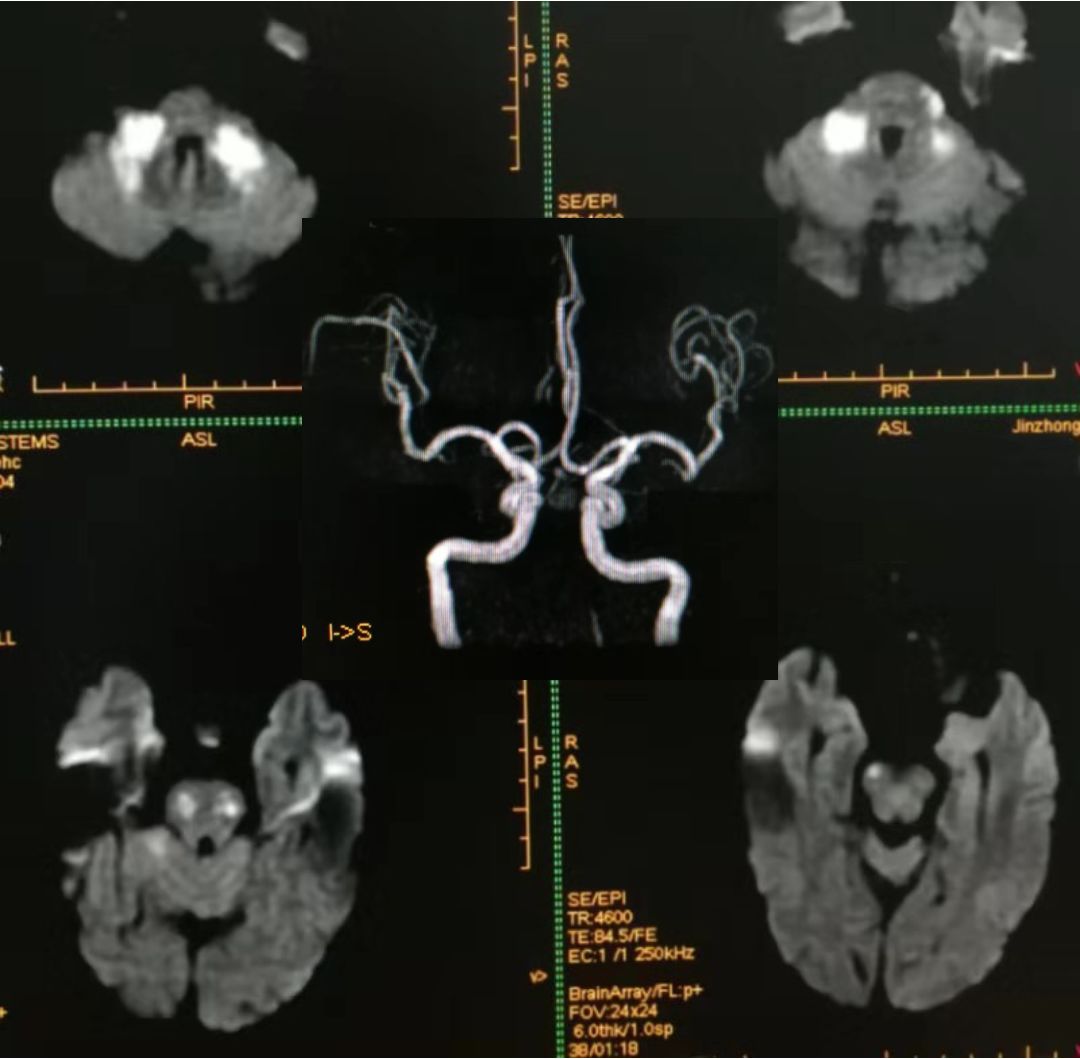

看两例文献图:

Case1:

Case2:

图自:Topics in Magnetic Resonance Imaging .Volume 23, Number 5, October 2014

影像学可见双侧颞、顶叶及右侧额叶多发散在皮层下白质病变,长T2,DWI高信号,ADC高信号。疾控中心HIV-1抗体:阳性,CD4+64cell/ul。

其影像学表现常位于白质,如脑室旁、半卵圆中心,呈对称、弥漫、云雾样白质异常,病灶可延伸至灰白质交界处。